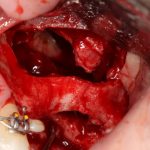

Кстати, обрати внимание на ширину альвеолярного гребня (левая картинка). Она чуть меньше 3 мм. Это объясняет, почему я засомневался в возможности установки имплантатов одновременно с остеопластикой. Понятно и без КЛКТ.

Наперво, мне нужно удалить разрушенный зуб и получить костный аутотрансплантат.